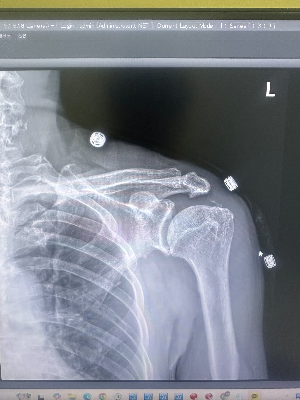

1차 의료기관에서 7년째 어깨 사진을 찍고 있는 현직 방사선사로서, 환자분의 얼굴 표정과 팔을 부여잡은 자세만 봐도 제 머릿속에는 이미 강력한 '용의자' 하나가 떠올랐습니다. 그리고 엑스레이 버튼을 누르고 모니터에 사진을 띄운 순간, 제 예감은 100% 적중했죠. 환자분의 어깨를 밤새 괴롭힌 범인은 오십견이 아니라, 엑스레이 사진에 선명하게 찍힌 '하얀 돌멩이'였습니다. 오늘은 방사선사들이 사진 딱 한 장만 보고도 환자의 극심한 고통에 고개를 끄덕이게 되는, 어깨 통증의 양대 산맥 '석회성 건염'과 '오십견'의 엑스레이 비밀을 속 시원히 파헤쳐 드릴게요.

석회성 건염은 어깨 힘줄(주로 극상근) 안에 칼슘 덩어리인 '석회'가 침착되면서 염증과 극심한 통증을 유발하는 질환입니다. 우리 몸의 뼈는 칼슘으로 이루어져 있어 X-ray 상에서 하얗게 보이죠? 마찬가지로 힘줄 안에 낀 돌멩이, 즉 석회 역시 뼈와 성분이 비슷하기 때문에 투명해야 할 어깨 힘줄 자리에 선명한 '하얀색 덩어리'로 찍혀 나오게 됩니다.

휴지기 & 흡수기 (통증의 절정): 뭉쳐있던 석회가 치약이나 젤리처럼 녹으면서 몸으로 다시 흡수되는 시기가 오는데, 이때 염증 반응이 폭발적으로 일어나 응급실에 갈 정도로 끔찍한 통증이 발생합니다. X-ray 상으로는 치약을 짜놓은 듯한 둥글고 뭉툭한 하얀 덩어리를 명확하게 확인할 수 있습니다.

환자분은 오십견인 줄 알고 오셨지만, 사진 한 장만으로 힘줄 위에 얹혀있는 하얀 돌멩이를 발견해 내는 것, 이것이 방사선사가 가장 직관적으로 통증의 원인을 찾아내는 순간입니다.